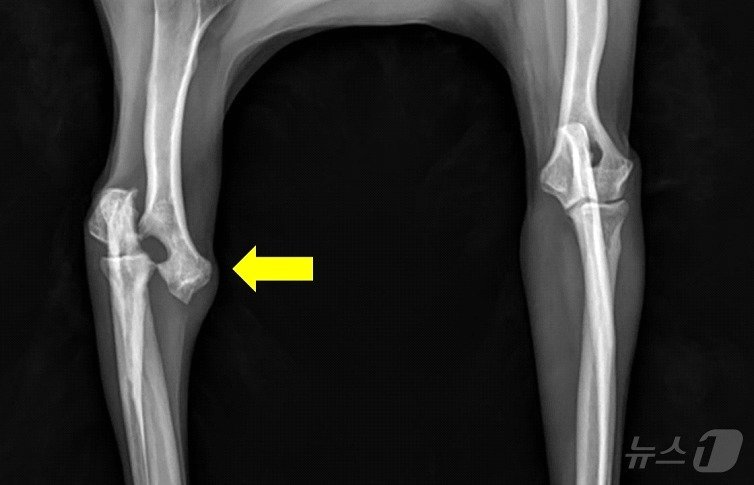

본문 이미지 - 낙상으로 인해 오른쪽 앞다리 골절상을 입은 강아지의 엑스레이 사진(VIP동물의료센터 제공) ⓒ 뉴스1

낙상으로 인해 오른쪽 앞다리 골절상을 입은 강아지의 엑스레이 사진(VIP동물의료센터 제공) ⓒ 뉴스1